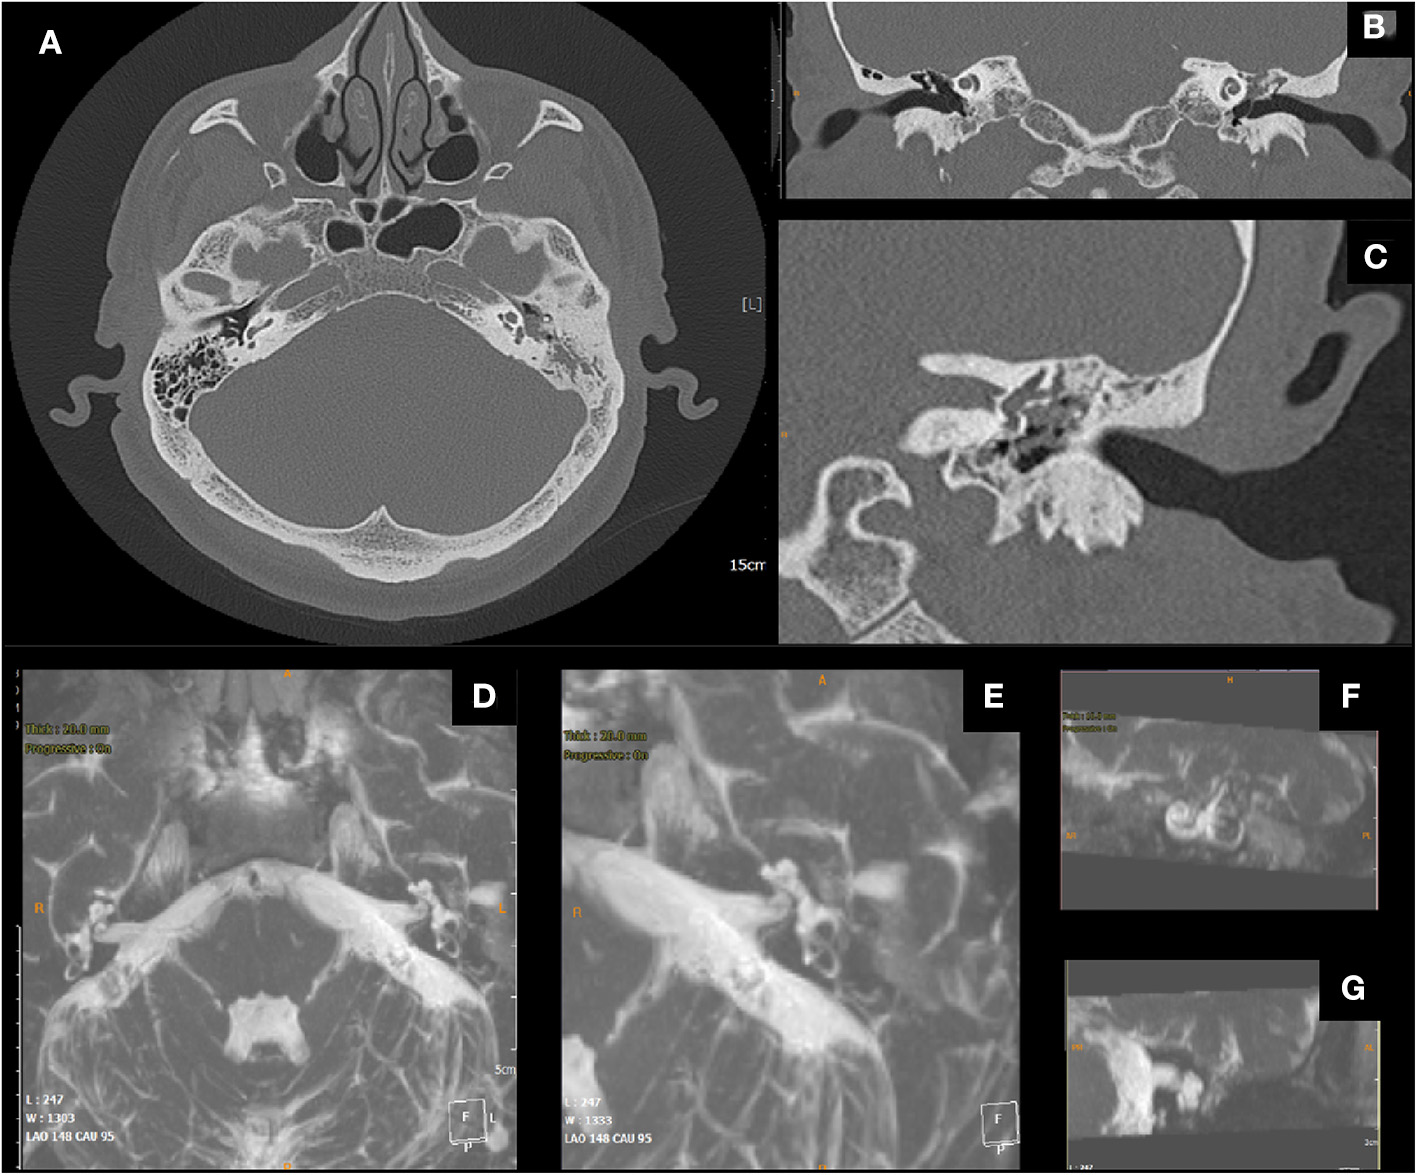

Figure 4

Male, 51 years old; (A) pre-operative axial CT scan, cholesteatomatous tissue eroding the wall of the lateral semicircular canal (LSC); (B) coronal CT scan, erosion of the LSC; (C) detail. (D) Post-operative Axial MRI 3D Fiesta 3D sequences (field of view 20 × 20 cm TR 4 ms; TE 2 ms; flip angle 55°); (E) post-operative MIP for visualization of the cochlea and the semicircular canals, detail of operated side, proper visualization of endocanal fluid showing its preservation (F,G) details.